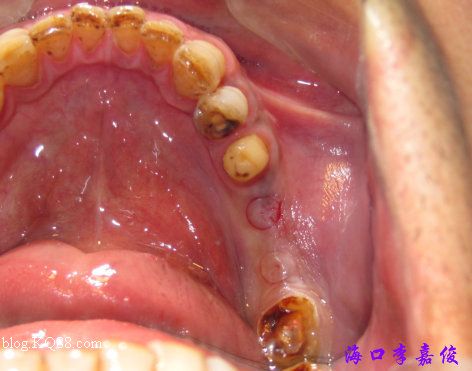

下牙術(shù)前

環(huán)切定位

下牙牙齦菲薄